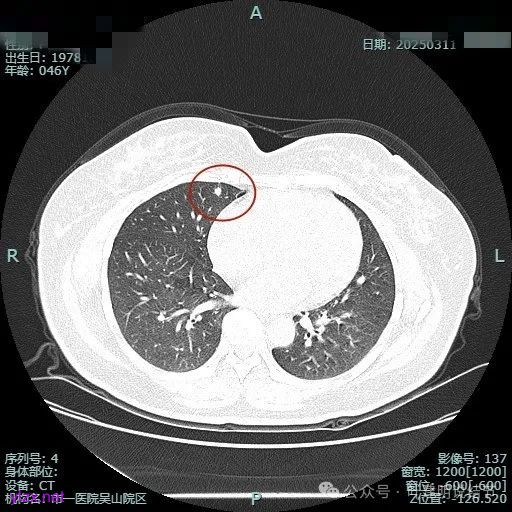

时间很快到了2025年3月,结友又来我门诊复查,我还以为她在别处开了刀了呢,结果并没有,说是与家人商量后决定吃中药三个月看看能不能好。我们来看看再复查的情况,中药有没有起作用:

总体感觉三处病灶边缘的淡磨玻璃成分好转不太明显了,实性成分较前略显致密点,大小与形态是说不上显著变化的。所以有几点可以肯定:1、消炎没有效;2、中药没有用;3、考虑多原发肺癌,且为浸润性腺癌可能性大些,得手术!

现病史:患者1年前于当地医院体检,行胸部CT提示肺部结节,平时无明显症状,无畏寒、寒战,无咳嗽、咳痰,无胸闷、胸痛,无恶心呕吐,无腹痛腹泻,无头晕头痛骨痛等不适,未予治疗。后定期复查,2025/3/11在杭州市肿瘤医院复查胸部(含纵隔)CT平扫+高分辨靶扫描:两肺纹理增粗,右肺下叶背段(SE4,IM95)可见实性结节,大小约14mm×10mm,可见分叶、胸膜凹陷征象。右肺中叶内侧段(SE4,IM137)可见实性结节,大小约6mm×5mm,可见胸膜凹陷征象。两肺内可见多发微小结节影,较大者位于右肺下叶内基底段(SE4,IM132)可见磨玻璃结节,大小约5mm×4mm。心影大小、形态正常;主动脉局部钙化。患者无畏寒、寒战,无咳嗽、咳痰,无胸闷、胸痛,无恶心呕吐,无腹痛腹泻,无头晕头痛骨痛等不适。为求进一步诊治来我院门诊就诊,拟“肺部阴影”收入我科。 患者起病以来,神志清,精神可,胃纳可,睡眠安,二便正常,体重近期无明显变化。 既往有“高血压”病史一年余,口服“苯磺酸氨氯地平片1#QD+奥美沙坦酯片1#QD治疗”控制血压,血压控制可。有“2型糖尿病”半年余,目前口服“达格列净片5mg1次/日”控制血糖。发现“肾病综合症”半年,目前无药物治疗。发现“右侧颈动脉及右锁骨下动脉斑块”半年,目前无药物治疗。有“高尿酸血症”病史,目前无药物治疗。